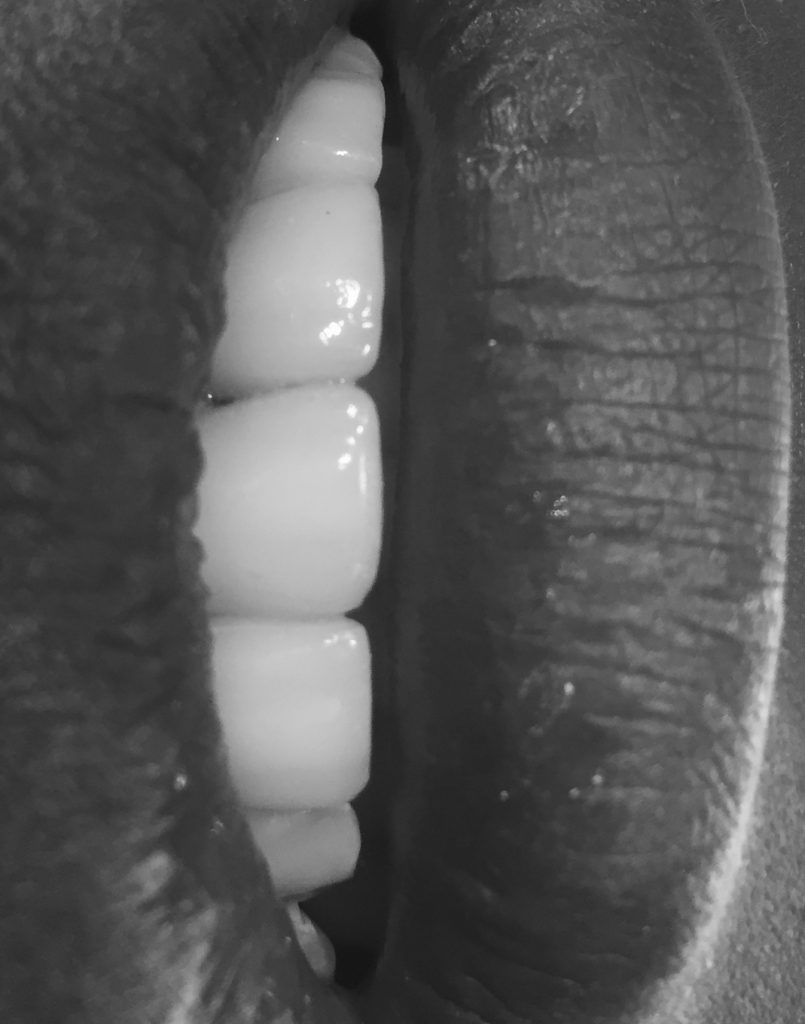

endodontic treatment was done, core buildup with dentisply metal post placed with glass ionomer cement, (fuji.). Joined ceramic crowns 12&11, 21&22 (ivoclar IPS eMax press LT A2) was done.